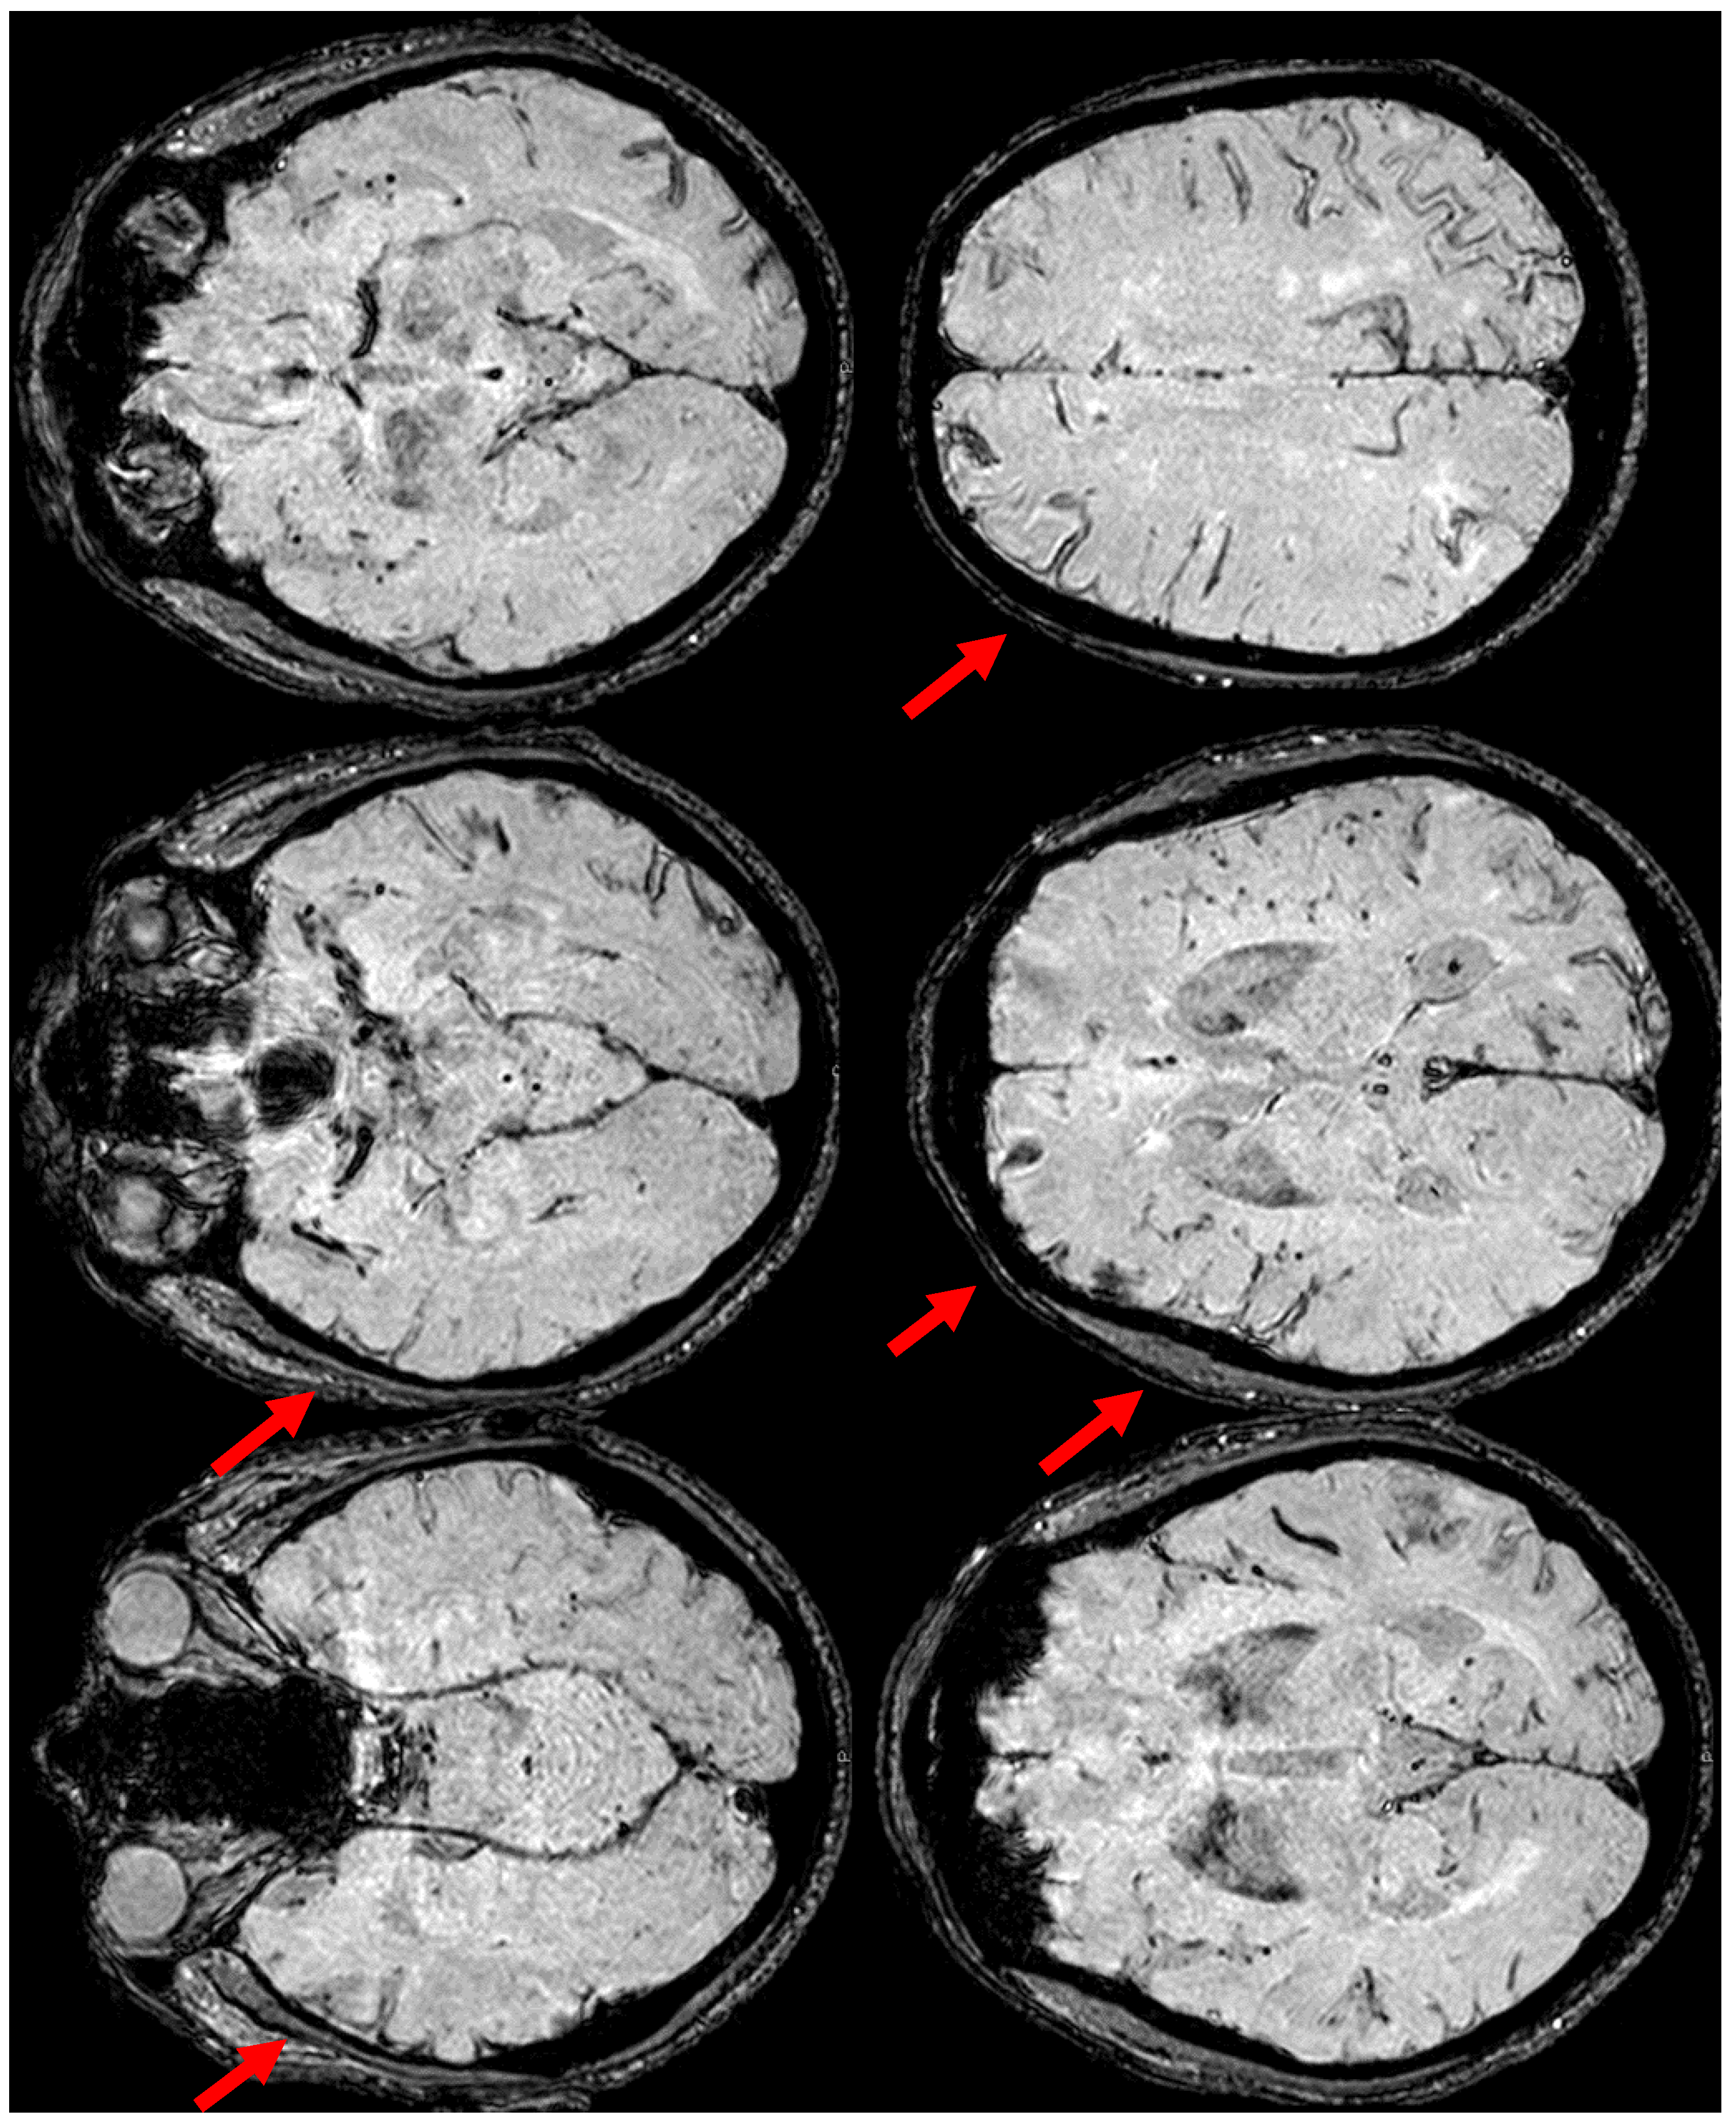

6. December 2017: Recurrent SAH